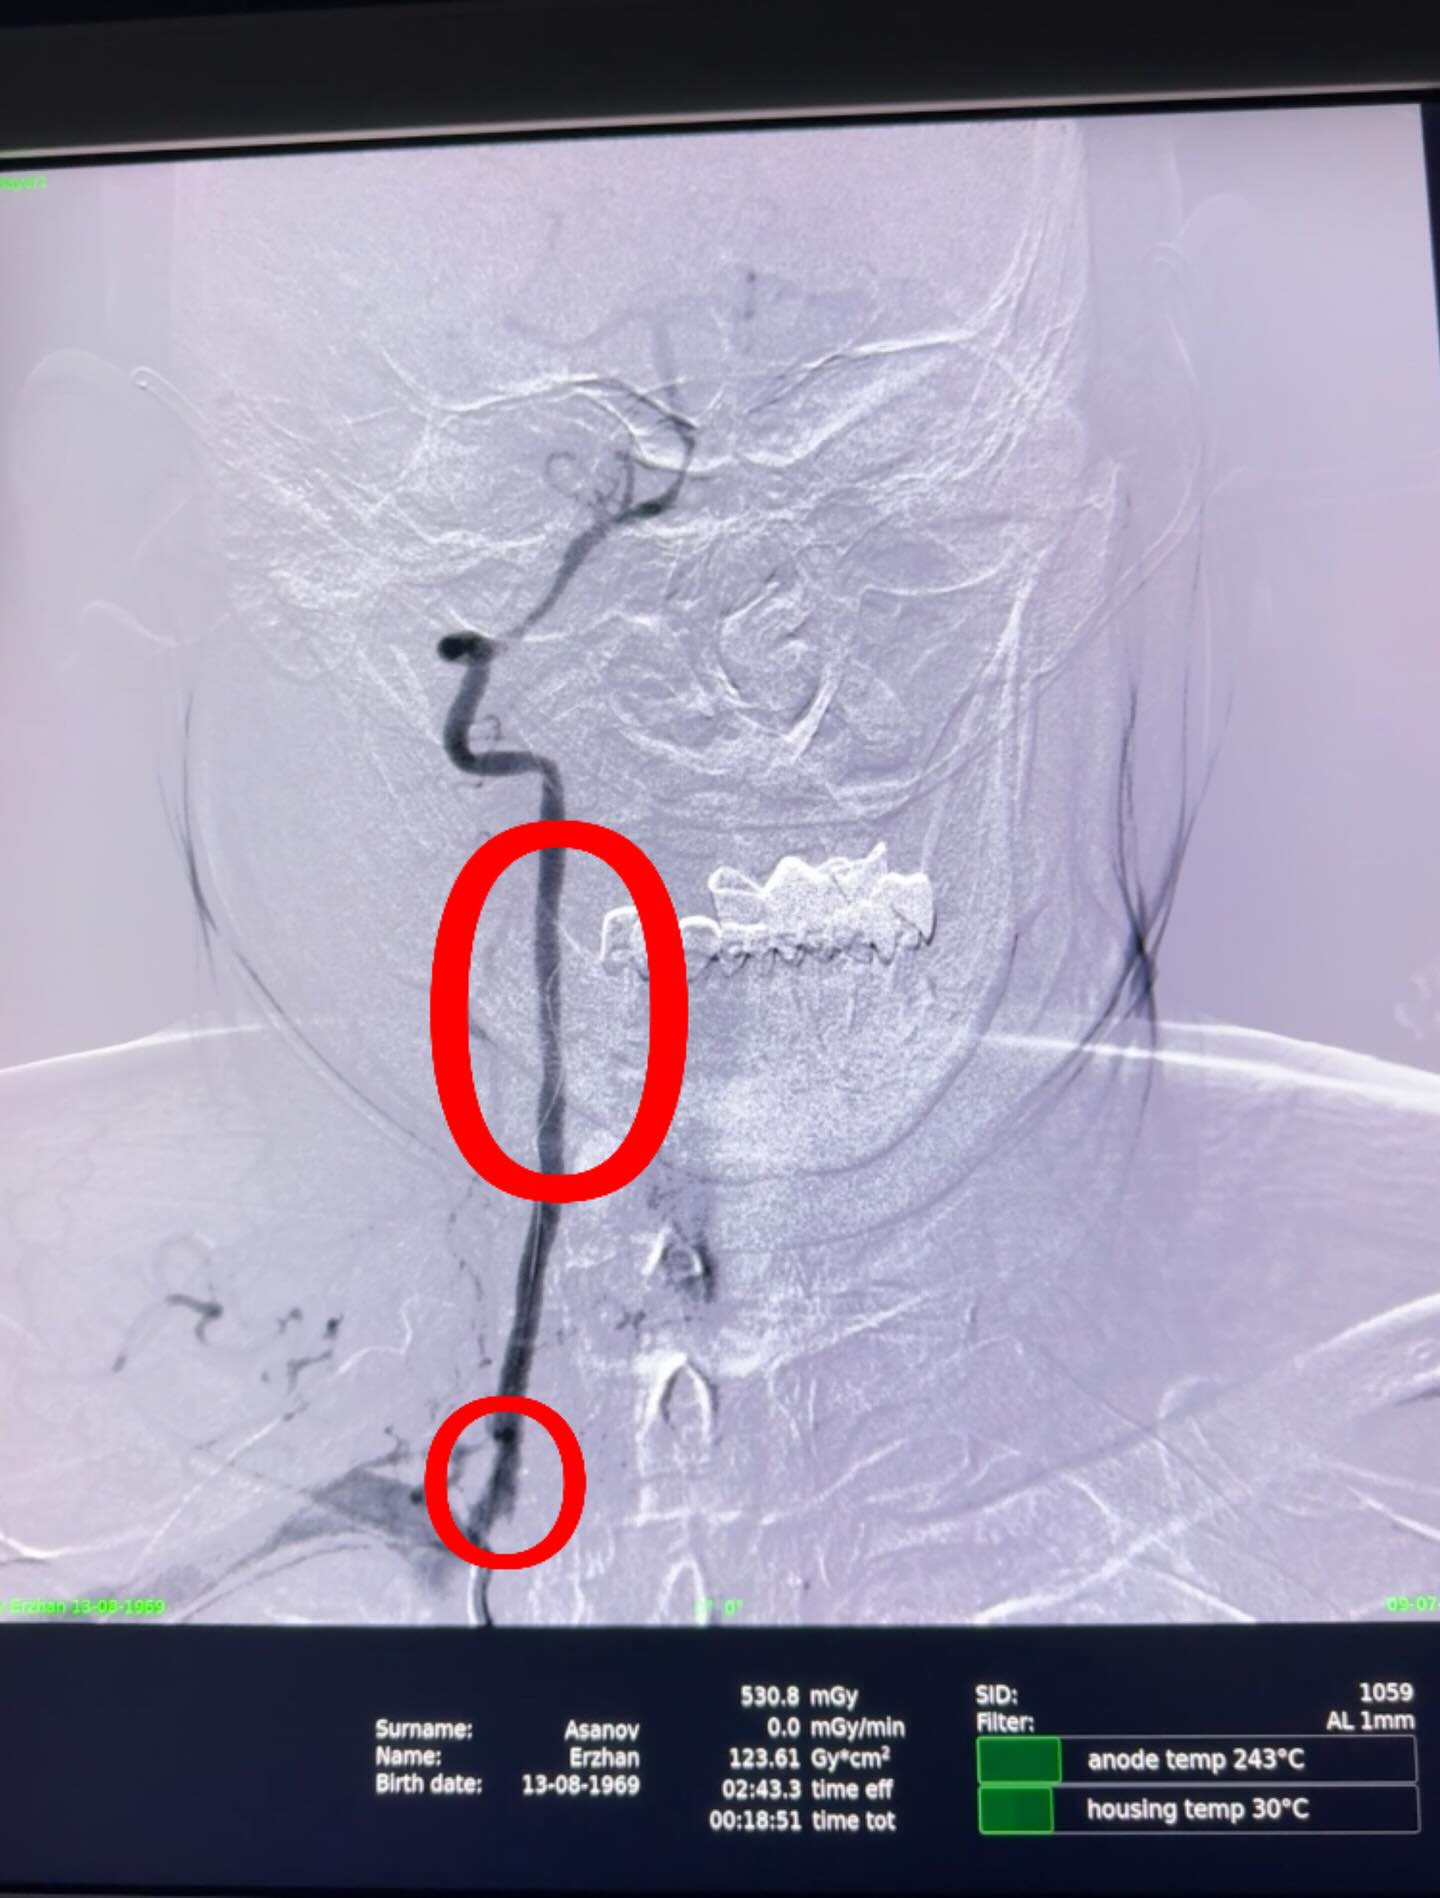

Сарыағаш аудандық орталық ауруханасының дәрігерлері ишемиялық инсульт диагнозы қойылған 55 жастағы науқасқа Омыртқа артериясын стенттеу отасын жасады. Өміріне қауіп төндіретін жағдай профилактикалық тексеру кезінде анықталған. Ота 1 сағатқа созылды.Ишемиялық инсульт — мидағы қан тамырының тромбпен немесе басқа бөгетпен бітеліп қалуы салдарынан болады. Бұл түрі инсульттің ең жиі кездесетін түрі — шамамен 80% жағдай.